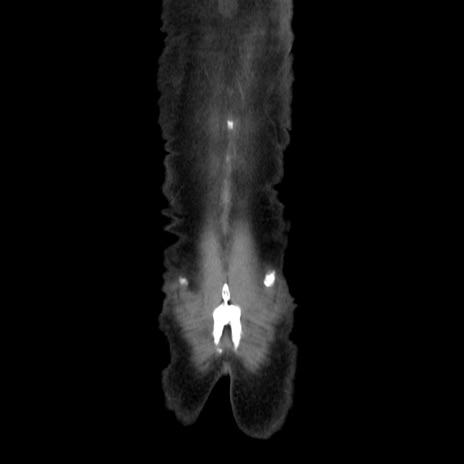

症例37(冠状断像)

【症例】40歳代 男性

【主訴】腹痛

【現病歴】4時間ほど前に電車に乗車中に臍部上より腹痛出現。徐々に増悪し起立困難となり、救急外来受診。生ものは数日食べていない。今朝お雑煮を食べた。

【身体所見】BT 36.8℃、BP 117/84mmHg、HR 91/min、SpO2 97%、苦悶様、腹部:臍上部広範囲圧痛あり、反跳痛±

【データ】WBC 8100、CRP 0.03